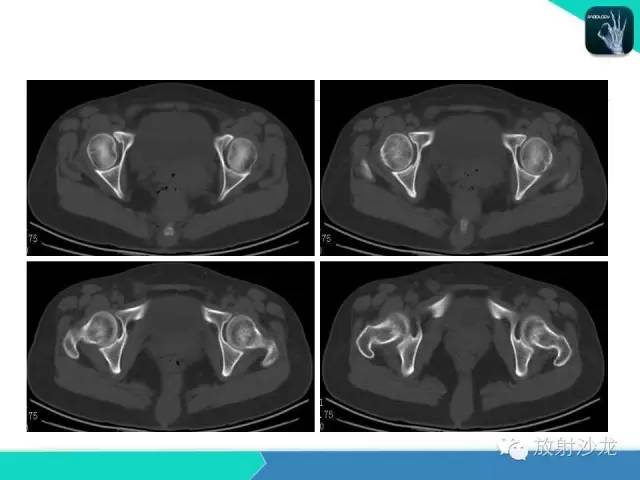

【病例】骶尾部表皮样囊肿1例CT